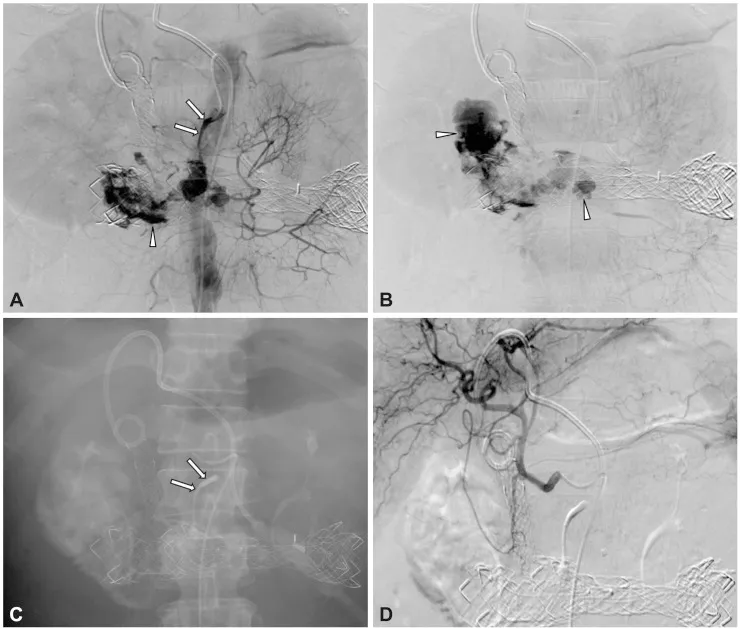

- Refractory Bleeds: Angiographic embolization, TIPS (variceal), or surgery.